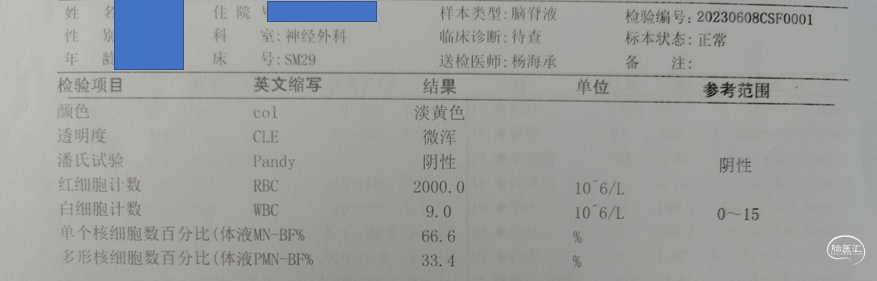

术后化验

2周后停抗生素